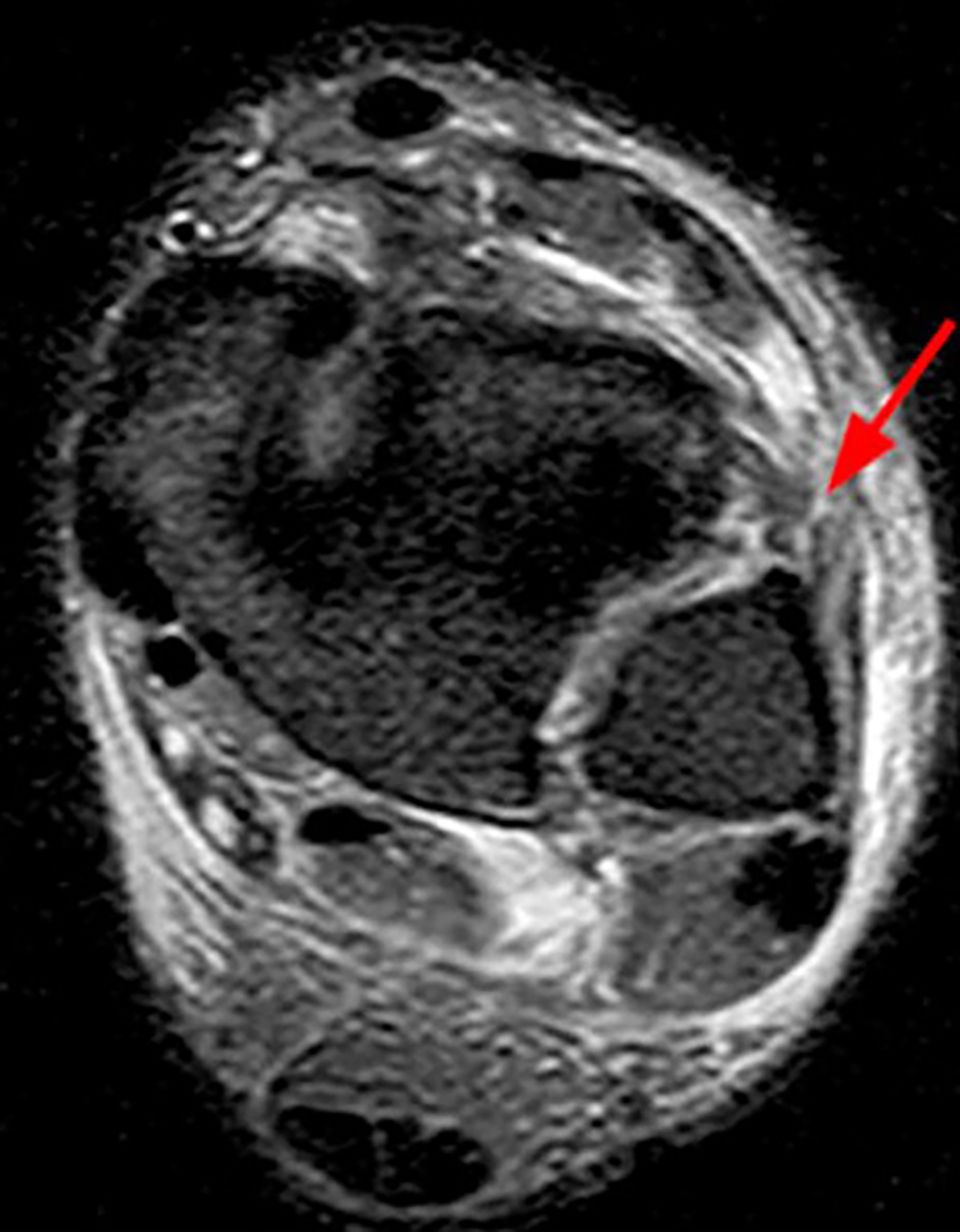

MR- Imaging (Figure 11)

MRI has been shown to effectively display the components of the syndesmotic complex with high interobserver agreement.[29] MRI has 93% specificity and 100% sensitivity for injury of the AiTFL, and 100% specificity and sensitivity for injury of the PiTFL compared with arthroscopy in acute injuries.[30] In diagnostic meta-analysis, the pooled sensitivity and specificity were 0.93 and 0.87 for MRI. [27]